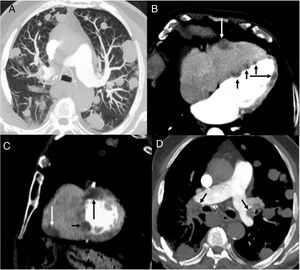

Our patient was an 87-year-old man, former smoker with a history of anticoagulated atrial fibrillation who underwent surgery for a malignant SFTP. Two years after surgery, a follow-up computed tomography (CT) scan of the chest revealed multiple bilateral pulmonary nodules compatible with metastases (Fig. 1A). CT-guided core needle biopsy confirmed that the pulmonary nodules were consistent with SFTP metastases. In the CT follow-up 1 month later, the pulmonary lesions had grown rapidly, and several nodular lesions were observed in the chambers of the heart, highly suggestive of cardiac metastases (Fig. 1B, C). A few days after the last CT follow-up, the patient was diagnosed with a massive bilateral pulmonary thromboembolism (Fig. 1D) and died a few hours later.

(A) Axial CT image of the chest (lung parenchyma window), showing multiple bilateral pulmonary nodules. (B and C) Axial (B) and sagittal (C) chest CT images (mediastinal window) showing several nodules in the right ventricular free wall (white arrow), interventricular septum (short black arrows) and left ventricular free wall (long black arrow). (D) Axial CT image of the chest (mediastinum window) showing filling defects in the pulmonary arteries (arrows).

Cardiac metastasis in SFTP is exceptional, and we have only found 1 documented case of left atrium metastasis by intracavitary extension from the left upper pulmonary vein. In our case, the rapid and extensive involvement of several chambers of the heart (coinciding with accelerated pulmonary progression) suggests a previously unreported hematogenous spread of the tumor. Although we were unable to confirm cardiac involvement with histology in our patient, we believe that imaging tests and rapid pulmonary progression (confirmed pathologically) reinforce the hypothesis of a metastatic origin of the cardiac lesions. We also believe that the subsequent pulmonary thromboembolism could be associated with tumor infiltration of the right heart chambers.